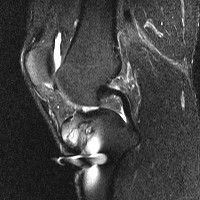

무릎 mri 간단히 봐주실 수 있으시나요 ㅠㅠ

안녕하세요 8년전 십자인대 수술하고 최근 무리한 운동에 무릎 불편감이 생겨서

mri 찍었습니다.

진단결과는 첫 찍은 병원에서 활액막염 이라는 진단을 받았습니다. 혹시 봐주실 수 있으실까요?

올라온 MRI가 단편적이라서 정확한 진단에 어려움이 있지만 십자인대에는 큰 이상이 있지는 않은것 같으며, 무릎관절내 물이 있는 것으로 보아 활액막염의 진단이 맞을 것 같습니다.

하지만 단편적인 영상이기 때문에 촬영병원에서 정확한 판독지 등을 받으시는 것이 좋겠습니다.